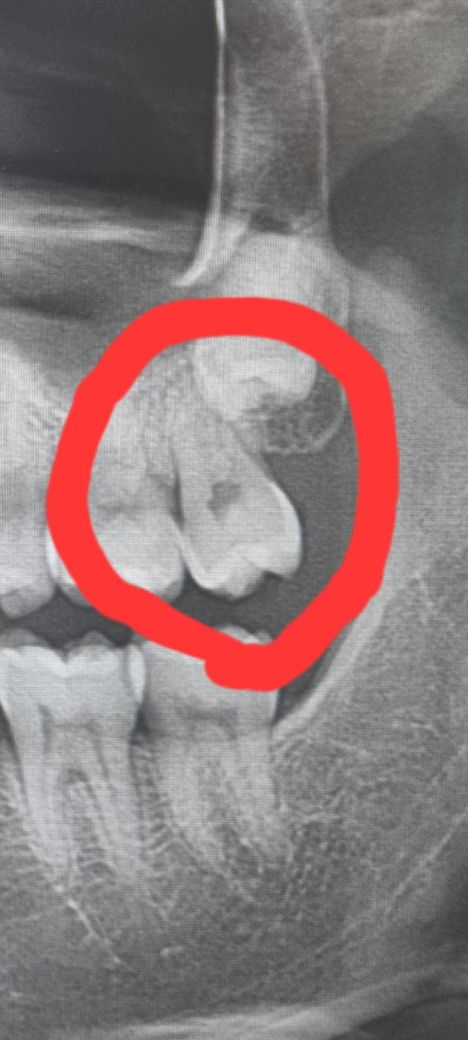

충치가 원래 X-ray 상으로는 잘 안보이나요? (x-ray, 치아 사진 첨부)

충치 치아는 왼쪽 위 맨끝 어금니 입니다.

치아사진으로는 좀 충치가 있어보이긴 하는데 저게 제 치아 사진인지도 의심이 되고 애먼 치아 인레이한게 아닌지 걱정되네요ㅠ

선생님들이 보기에는 충치가 있어 보이실까요?

• 1번 째 사진